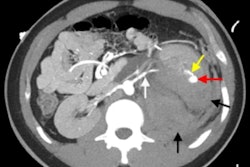

For a long time, CT characterization of kidney tumors was divided into classifying cystic masses using the Bosniak classification method and identifying macroscopic fatty elements allowing the diagnosis of angiomyolipoma, while diagnosis of carcinoma was based on tumors with a necrotic aspect or signs of local extension, according to Grenier.

Today, however, incidental findings of little solid masses during imaging are the main mode of diagnosing kidney cancer. Among these masses, the proportion of benign tumors is all the more important because they are small, he stated.